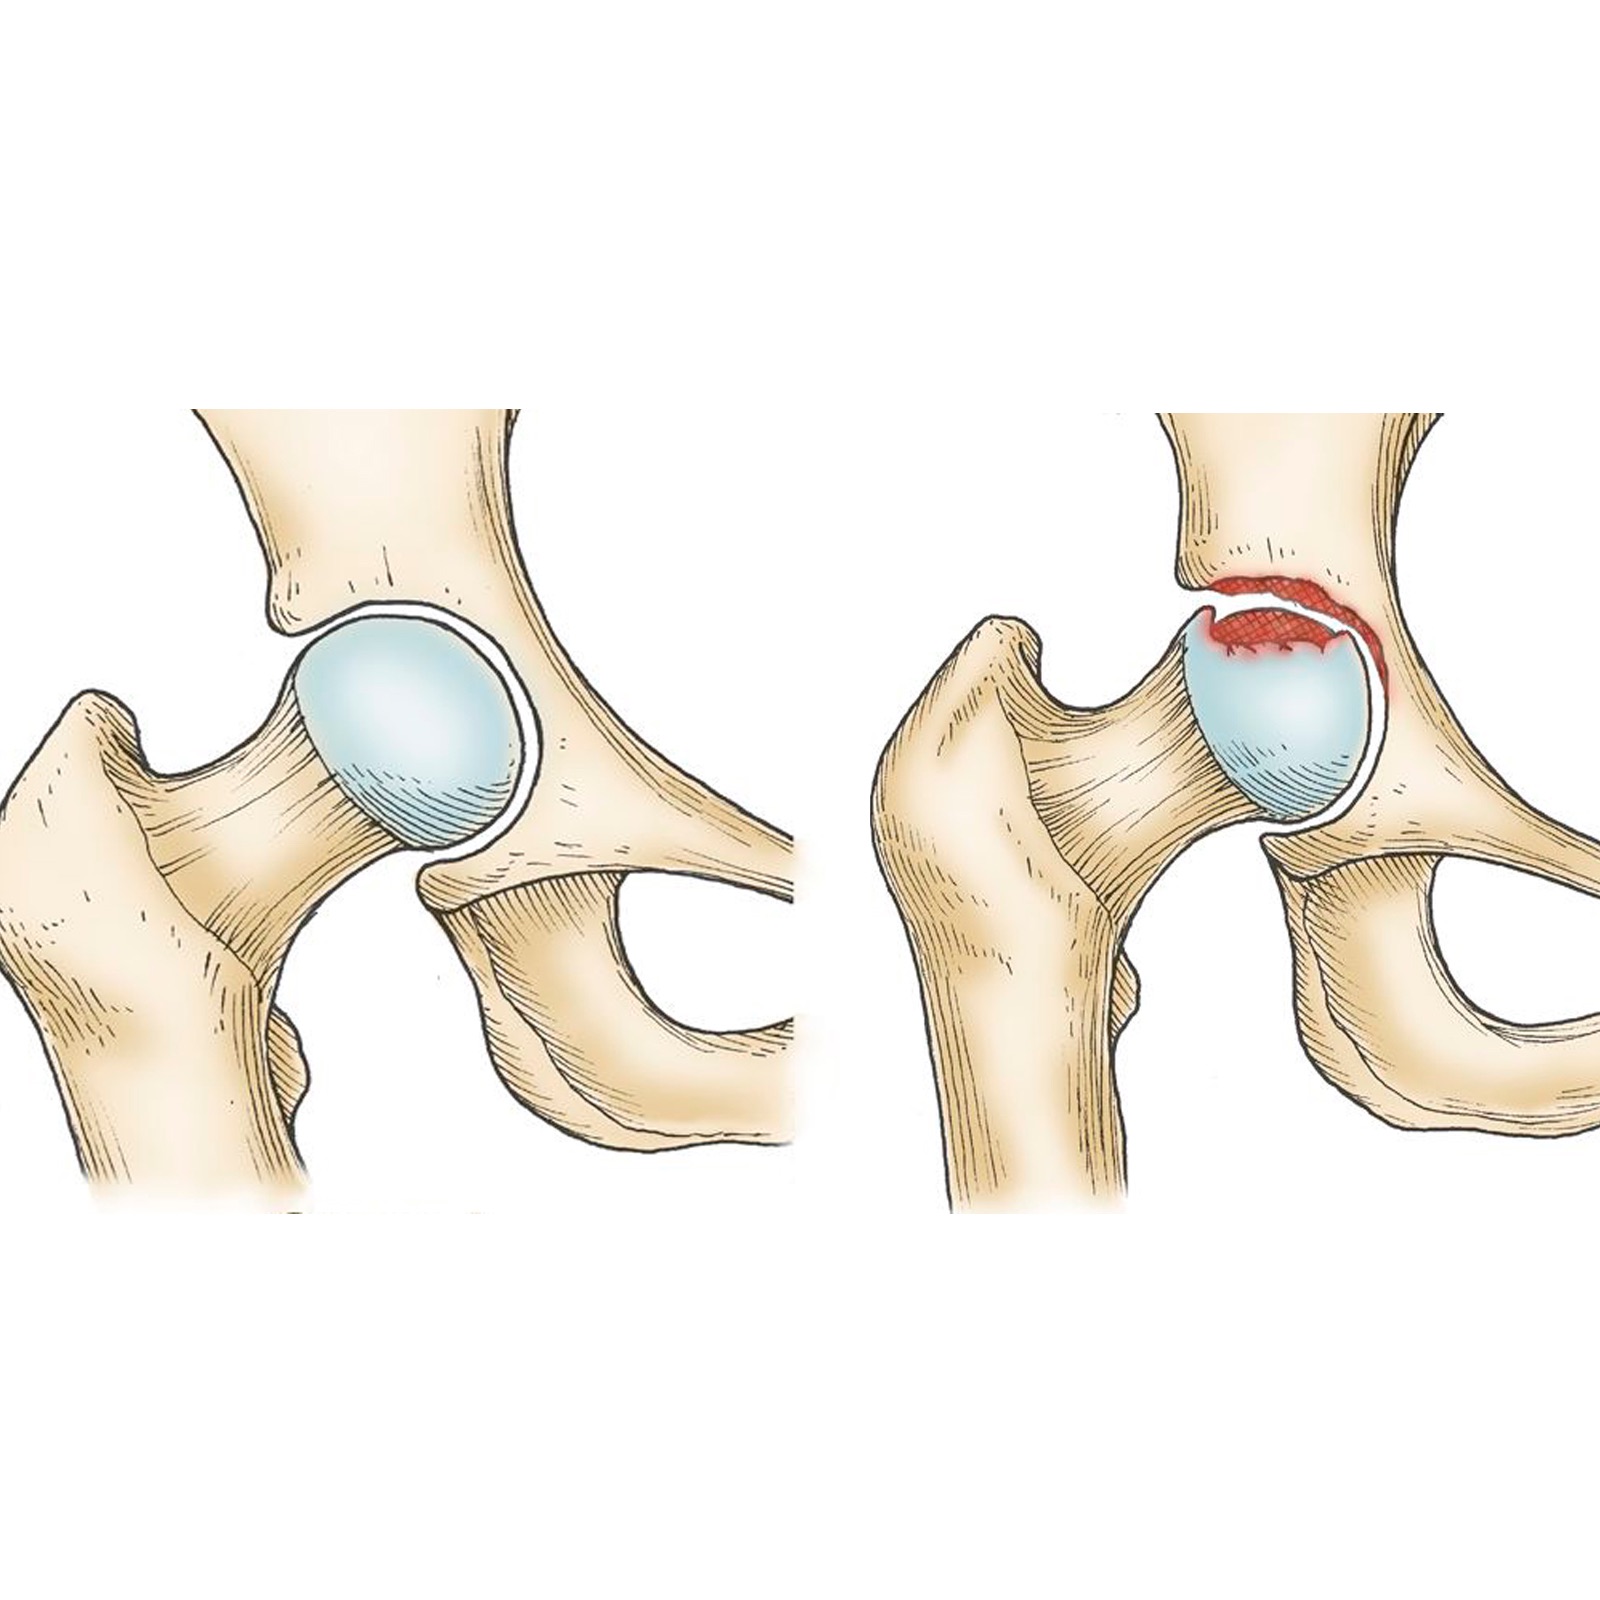

Медицинские снимки: рентген коленного сустава при остеопорозе